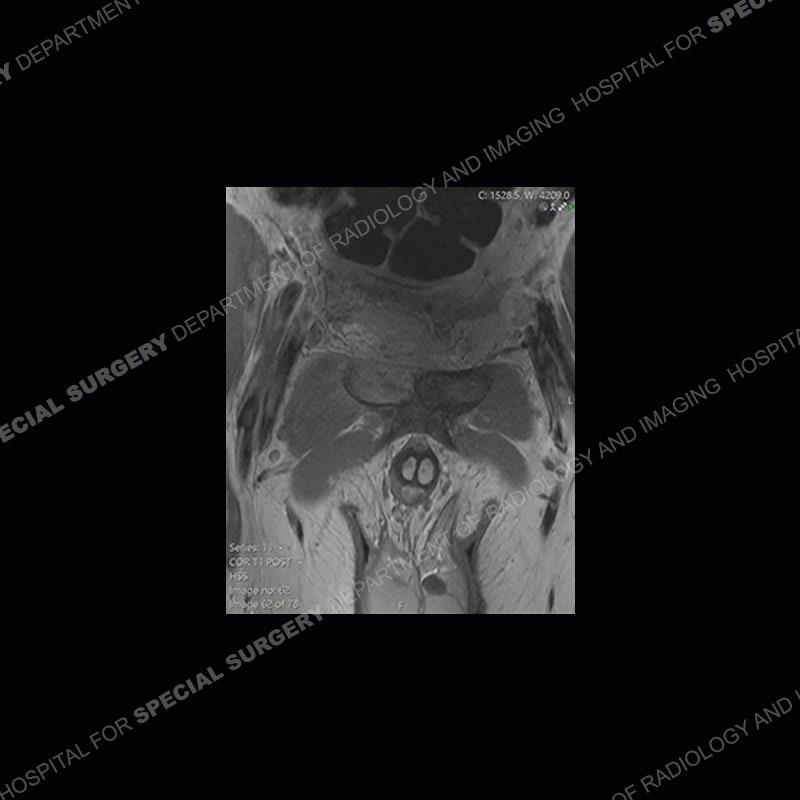

Subsequent MRI in a very short time interval shows markedly increased abnormality of the ramus and increased edema and “mass” of the soft tissue. Post contrast imaging shows multiple, rim enhancing collections of the soft tissue and similar albeit less conspicuous enhancing collection of the ramus.

This case was a bit surprising to all involved given that the young man is otherwise in good health and extremely active in sports. The original thought was this case was going to be an overuse injury or stress fracture. The pubic ramus with the adjacent physis acts as a metaphyseal equivalent and although not frequently thought of would be a reasonable location for infection/osteomyelitis. The first MRI was somewhat confusing as the process did not have an appearance of a stress injury or rectus adductor aponeurosis injury. The degree of edema of the bone and soft tissue together would be odd especially for a sports hernia process. Initially, the thought was of an aggressive process which could be infection or neoplastic. Particularly, the abnormal architecture of the inferior surface of the ramus looked like a destructive process.

The repeat MRI, with the marked degree of increased abnormality of the bone and soft tissue shifted the diagnosis to a high degree towards infection. Even the most aggressive of neoplasms would not have that the degree of change in a 3-day time span. The CT study was shown before the repeat MRI but actually occurred just after the repeat MRI. It helped confirm the destructive process of the ramus and particularly the abnormal architecture along the inferior margin. The patient went on to have a CT guided aspiration of one of the soft tissue collections with 4cc of purulent fluid obtained. A surgical irrigation and debridement of the bone and soft tissue was performed. A PICC line was placed and the patient is currently undergoing IV antibiotic treatment with a possible repeat irrigation and debridement.